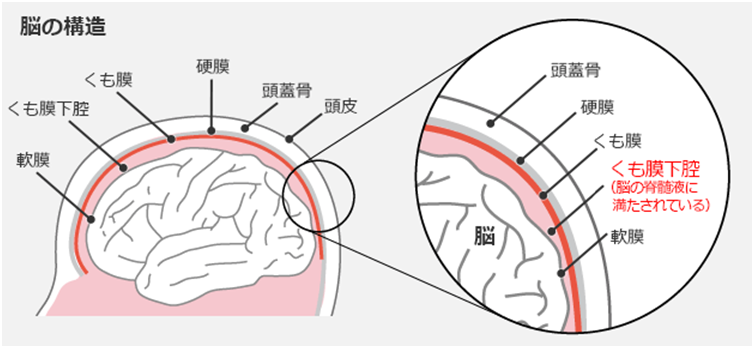

くも膜下腔内化学療法は、脳脊髄液 (CSF) を標的とする癌治療の一種です。 CSFは、主に脳の心室によって生成される無色の液体です。脳と脊髄を取り囲んで損傷から保護します。

これは、中枢神経系の周りに血液脳関門と呼ばれる保護層があるためです。この障壁により、毒素やその他の有害物質の侵入を防ぎながら、必要な栄養素と酸素が脳に入ることができます。

残念なことに、血液脳関門は、経口投与または点滴による抗がん剤の多くをブロックし、その効果を低下させる可能性もあります。

医師は、より標的を絞った化学療法を中枢神経系に施すために、くも膜下腔内化学療法を選択する場合があります。